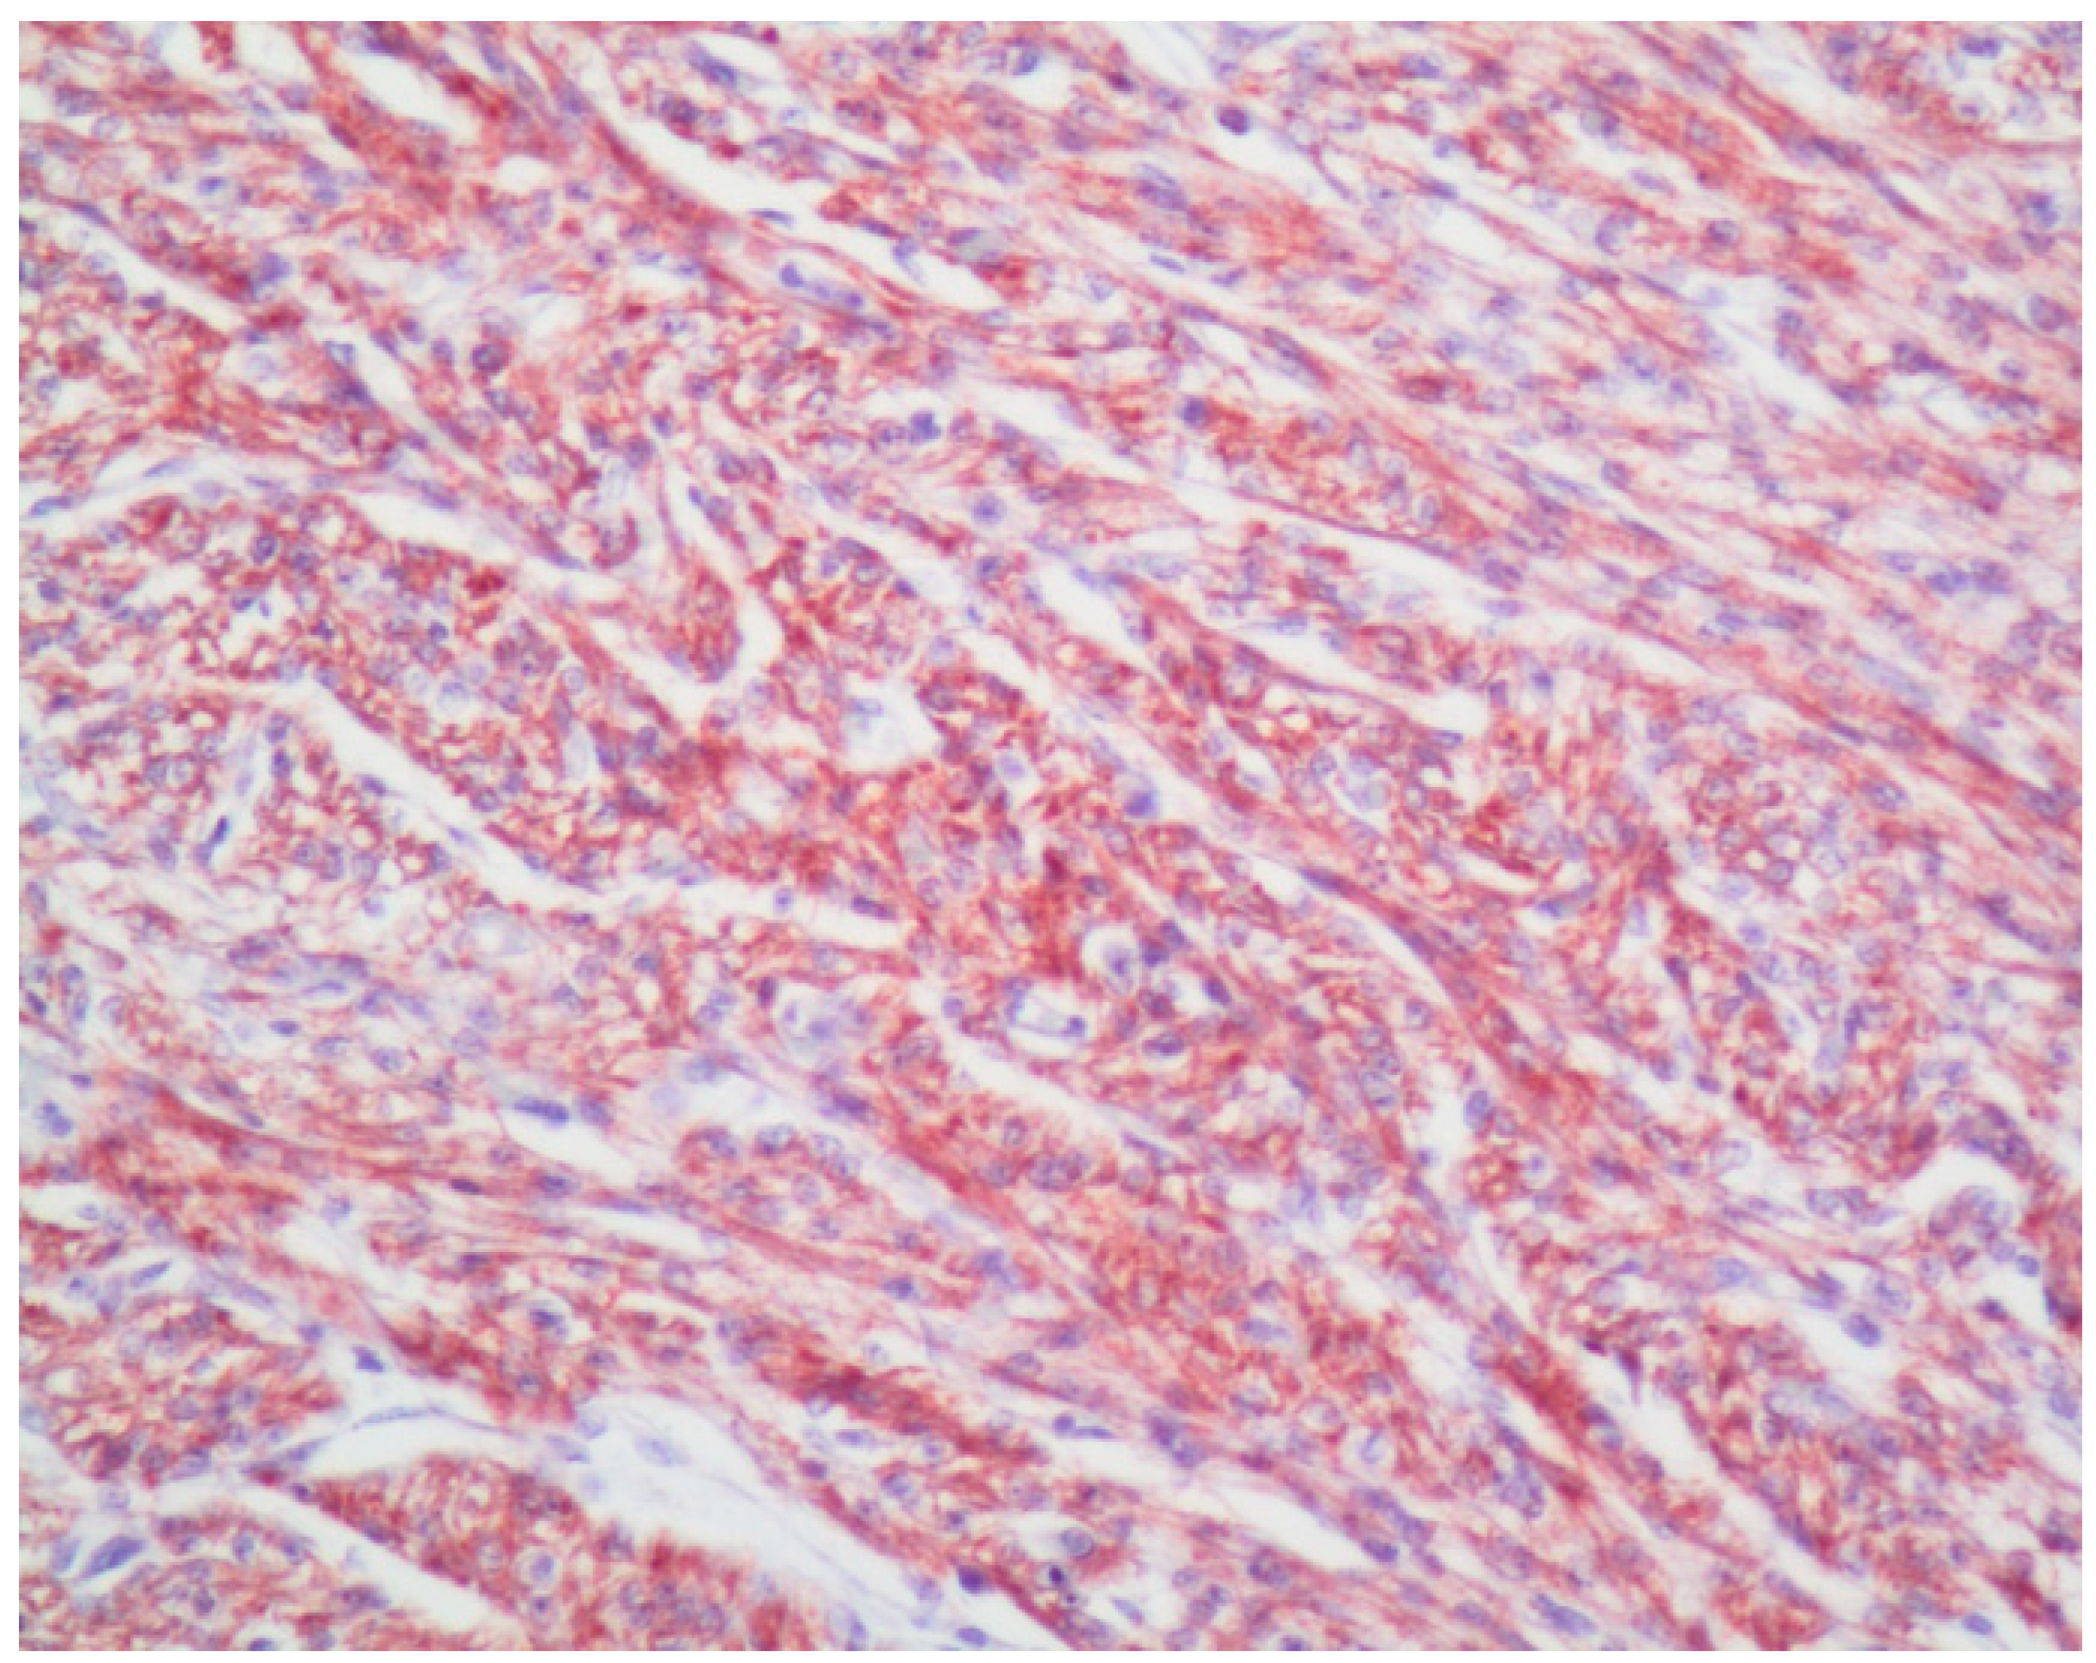

2.2. Immunohistochemistry and Immunomorphometry

3.3. VDAC1 Expression